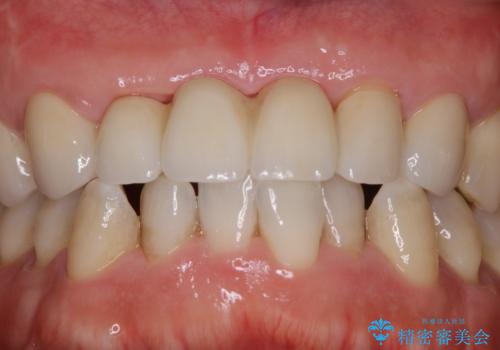

セラミックのチェックと合わせてPMTC